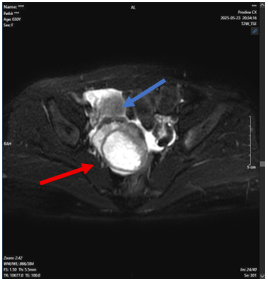

Dựa vào những tổn thương nghi ngờ trên siêu âm, chúng tôi tiến hành chụp cộng hưởng từ vùng chậu:

Hình 7: Hình ảnh cộng hưởng từ vùng chậu

Buồng trứng phải có cấu trúc kích thước ~ 34x25 mm, trung tâm có ổ ngấm thuốc kém.

Nằm cạnh buồng trứng phải có khối kích thước ~ 51x47mm, trung tâm có tín hiệu dạng dịch.